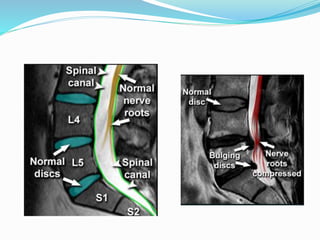

 Spine

 PIVD

 Cord compression